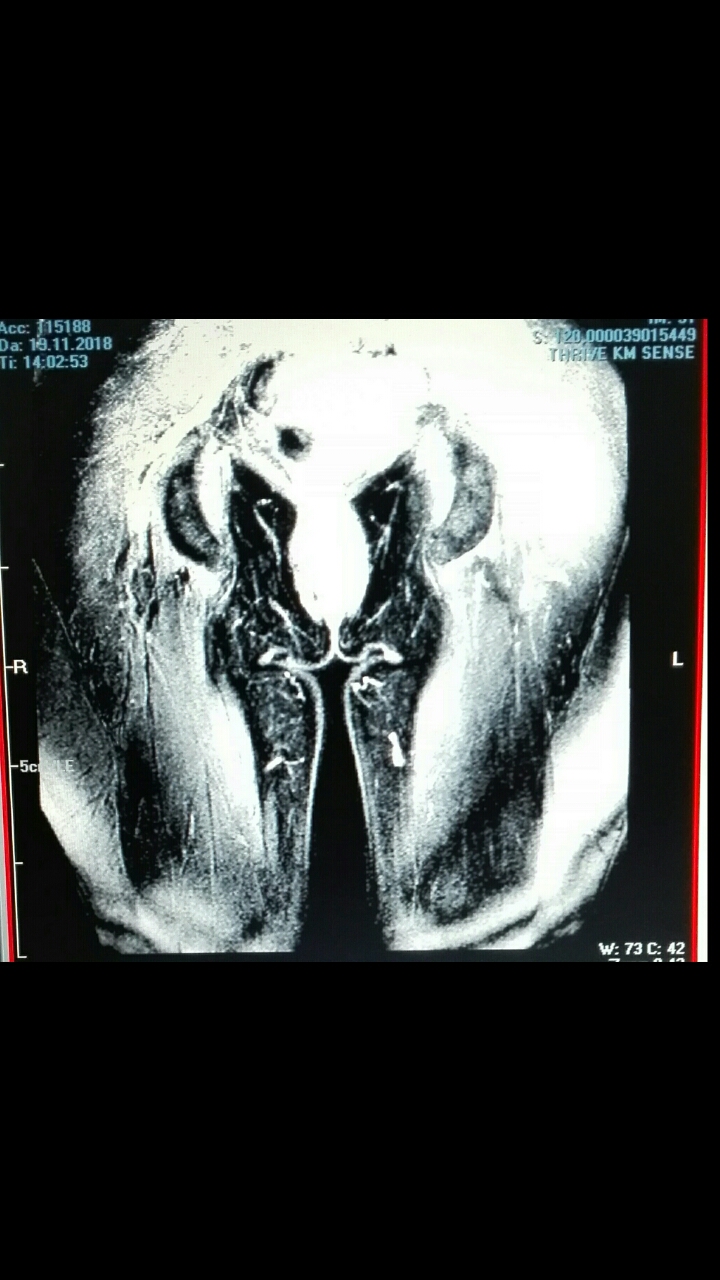

Das neue MRT mit KM zeigt deutlich Gewebeverletzungen in Hüfte, Oberschenkel, die zur rechten Seite ziehen. Aber rechts deutlich weniger sind. Genau wie beim Ultraschall Elastrographie.

Das ist ein neues MRT-Bild vom unteren Becken + Oberschenkel.